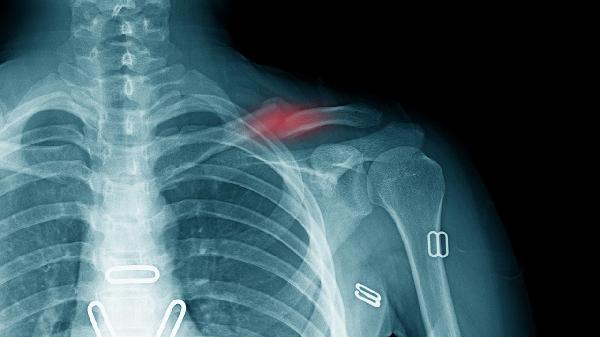

线性无移位骨折恢复较快,约4-6周可尝试抬臂;粉碎性或明显移位骨折需更长时间骨痂形成,通常需8-12周。儿童青枝骨折因骨膜完整,愈合速度较成人快30%-40%。